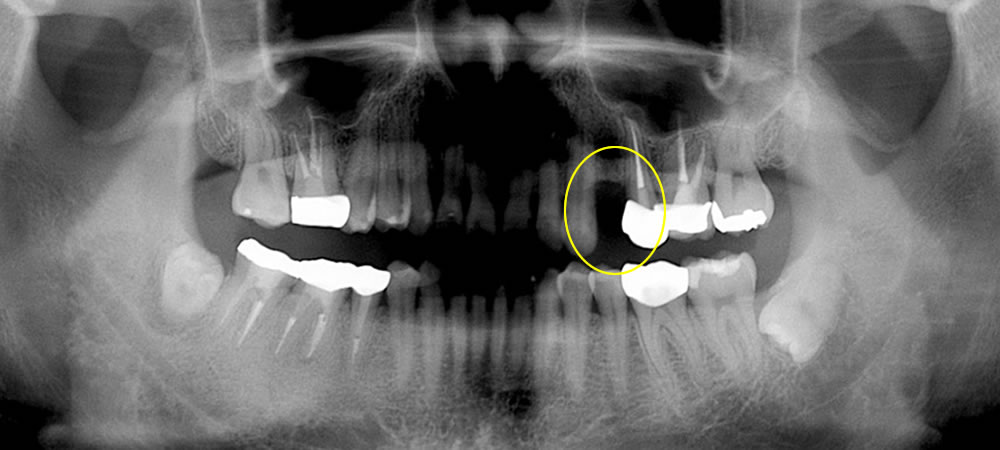

インプラント治療前のレントゲン検査

オペ前のレントゲン画像です。抜歯後の骨の状態は良好で高さ、幅もあるのでインプラントは問題なくできると判断しました。

インプラント手術前後のレントゲン

インプラント手術前後のレントゲン写真です。しっかりと骨の中にインプラントが埋入されているのがわかります。